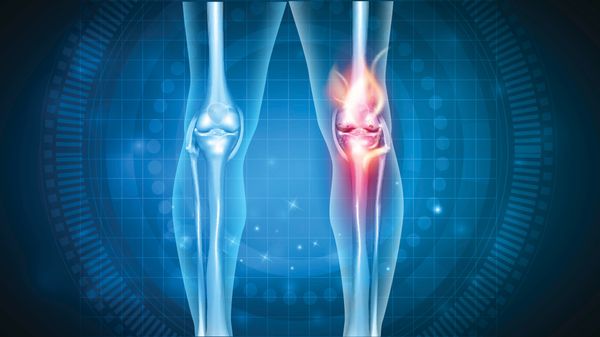

Gonarthrose des Kniegelenks

Das Knie besteht aus mehr als Oberschenkelknochen (Femur) plus Schienbeinknochen (Tibia): Meniskus, Kniescheibe (Patella) sowie ausgeprägte Sehnen und Bänder verkomplizieren den Aufbau. Verschleißerscheinungen treten in den verschiedenen Kompartimenten auf. Femoropatellarathrosen zwischen Oberschenkelknochen und Kniescheibe behindern das Treppensteigen. Mediale und laterale Femorotibialarthrosen auf Innen- und Außenseite von Oberschenkel und Schienbein schmerzen bei Beugen oder Strecken.Typisch für Gonarthrosen ist ein Krankheitsbeginn im fünften Lebensjahrzehnt. Je weiter die Arthrose fortschreitet, desto häufiger breitet sie sich auf das gesamte Knie aus (panartikuläre Gonarthrose).